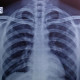

Alodokter.. Izin bertanya. Foto toraks dgn Ground glass Opacity pada pasien kontak kasus konfirm Covid19 4 hari sebelumnya. Referensi yg saya dapat GGO ditemukan pada CT Scan. Ada referensi GGO pada foto toraks?!

Mata saya tidak melihat dan menemukan gambaran GGO pada Cxr tersebut. Kesan dalam batas normal.

GGO lihatnya di HRCT scan toraks tanpa kontras. Perlu diketahui bahwa GGO bukan mutlak punya covid tp bs ditemukan pd kondisi ekspirasi, edema paru,pneumonia bakteri,PCP, bahkan adeno ca paru

Maaf dok setau saya gambaran GGO ditemukan pada ct dok, dan tetap pada rontgen gambaran infiltrat seperti pasien TB atau BP yg terkonsentrasi di sisi lateral. Dan foto ini sepertinya normal dok